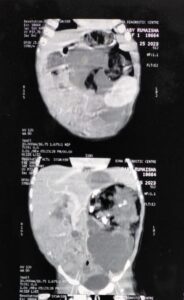

लखनऊ। प्रयागराज के बाद लखनऊ के KGMU में भी ‘फीटस इन फीटू’ का एक केस सामने आया है। यहां पीडियाट्रिक सर्जरी के विभागाध्यक्ष प्रो. जेडी रावत व उनकी टीम ने दुर्लभ सर्जरी कर 13 माह की बच्ची के पेट से बड़ी गांठ को निकाला है। गांठ में हड्डी एवं शरीर के अन्य भाग बाल, आंत भी विकसित हो गए थे। पिछले दिनों प्रयागराज में भी फीटस इन फीटू का मामला सामने आया था, वहां सात माह के शिशु की सर्जरी की गयी थी।

यही नहीं बच्ची कुछ खा पी भी नहीं पा रही थी, जिसकी वजह से उसका वजन भी लगातार कम हो रहा था। परेशान मां-बाप गंभीर हालत में बच्ची को लेकर लखनऊ स्थित KGMU ट्रॉमा सेंटर पहुंचे। उसके बाद यहां बच्ची को पीडियाट्रिक सर्जरी के प्रोफेसर जेडी रावत की टीम की निगरानी में भर्ती किया गया। जांच के बाद पता चला कि बच्ची के पेट में बड़ी सी गाँठ है जो बड़ी नसों, धमनियां, बाएं गुर्दे तथा बाएं फेफड़े की झिल्ली से चिपकी हुई थी।

प्रोफेसर जेडी रावत एवं उनकी टीम ने बच्ची का 31 जुलाई को ऑपरेशन किया। कैंसर की गाँठ को सफलता पूर्वक बड़ी नसों, धमनिया तथा बाएं गुर्दे को बचाते हुए निकाल दिया। जिसमें 3 घंटे का समय लगा। बच्चा वार्ड में अभी स्थिर हालत में है तथा स्वास्थ्य में सुधार हो रहा है।

इस बीमारी को फ़ीटस इन फिटु (Fetus in fetu) कहते हैं। क्योंकि इस गाँठ में हड्डी एवं शरीर के अन्य भाग बाल, आंत भी विकसित थे। यह एक विरल असाधारण बीमारी होती है। जो कि पांच लाख में से एक बच्चे में पायी जाती है।